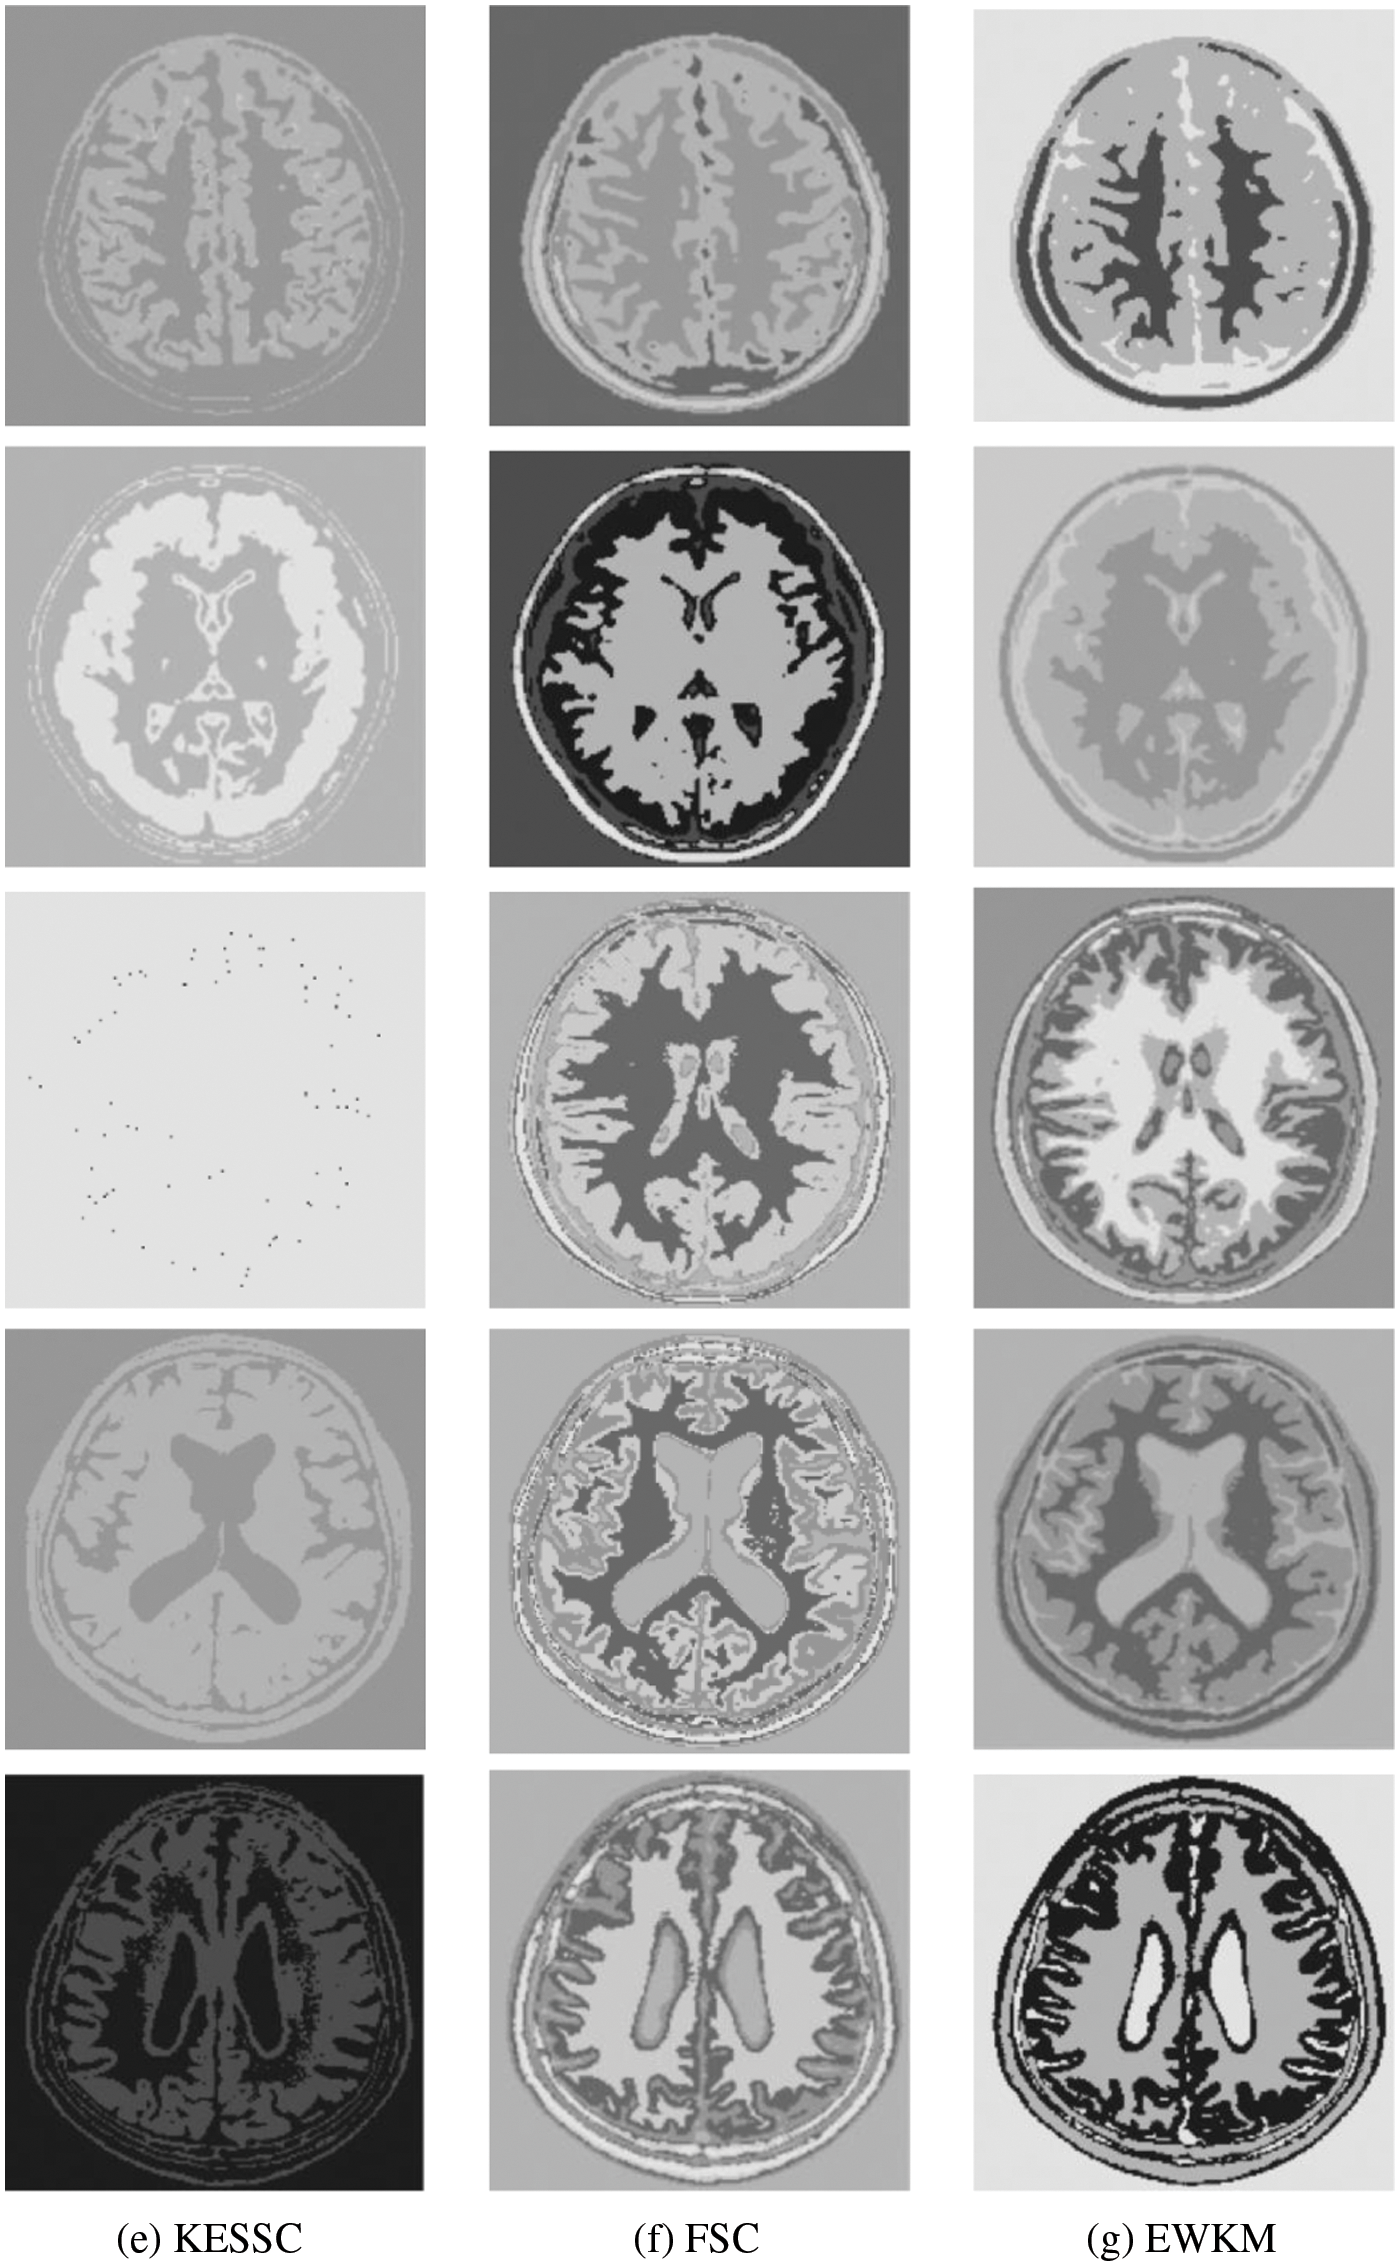

For the experiments in the previous subsection, experiments were conducted on publicly available medical brain MR images. In this chapter, the brain MR images provided by the imaging department of the First People’s Hospital of Changshu, Suzhou, China, were selected. In Fig. 4, (a) is the original image provided by the hospital, and the data were acquired by a Philips 3.0T standard MRI scanner with a 3D T1-weighted gradient echo sequence map. The parameters during scanning were as follows: TR = 5.5 ms, TE = 2.7 ms, layer spacing 0.3 mm, layer thickness 1.3 mm, FOV = 35 cm × 35 cm, image size 200 × 200 pixels, and each scan time was 60 s. In this paper, MR images of the clinical brain are used for experiments, and a variety of soft subspace clustering algorithms are used for comparison. The segmentation effect is shown in Fig. 4.

Figure 4: (a) shows the real brain MR image provided by the hospital, (b) shows the segmentation effect of the proposed algorithm, (c) shows the segmentation effect of the ESSCND algorithm, (d) shows the segmentation effect of the ESSC algorithm, (e) shows the segmentation effect of the KESSC algorithm, (f) shows the segmentation effect of the FSC algorithm, and (g) shows the segmentation effect of the EWKM algorithm

The second row in Fig. 4 is the real MR image provided by the hospital, and the image contains 5 classes: 0 = Background, 1 = CSF (cerebrospinal fluid), 2 = Gray Matter, 3 = White Matter, and 4 = Skull; these 5 classes are segmented by clustering segmentation. Table 2 shows that the GAESSCND algorithm is able to segment the 5 classes with clear boundaries, while the rest of the comparison algorithms have poor results in the face of noise processing, with mixed boundaries and mis-segmented brain tissue.

Due to the lack of truth maps in the dataset provided by the hospital, the evaluation metrics were chosen from the internal evaluation metrics in MATLAB. Davies–Bouldin index (DBI) [48] silhouette coefficient (SC) [49].

In Table 3, it can be seen that the proposed GAESSCND algorithm segmentation yields the best results with the smallest DBI coefficient, the strongest similarity in each cluster class, and the largest contour coefficient SC, segmenting significantly and outperforming other clustering algorithms. In the experimental process of Fig. 3, the KESSC algorithm has most of the kernel space with zero, resulting in obvious deviation of the weight contribution; the experimental segmentation effect is poor, and the corresponding evaluation index result is NaN.